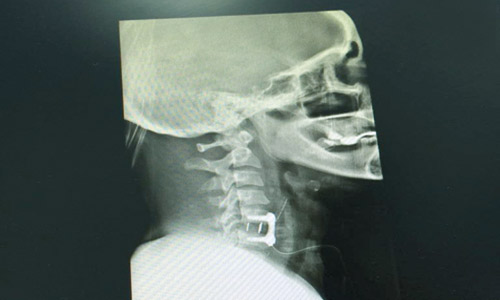

نجح المستشفي السعودي الألماني بالرياض في إنقاذ مريضة سعودية من الشلل وضعف مزمن بالأطراف العلوية.. وكانت المريضة قد حضرت إلى المستشفي وهي تعاني من كسر وخلع بالفقرات العنقية الخامسة والسادسة مع ضعف بالأطراف العلوية، وبعد عرض الحالة على الدكتور حازم فريد إخصائي جراحة العمود الفقري، قرر الإخصائي إجراء عملية جراحية لإصلاح الخلع وتثبيت الفقرات العنقية بواسطة شريحة ومسامير. هذا وقد تماثلت المريضة للشفاء التام عقب إجراء العملية الجراحية، حيث أجرت المريضة عمليتين جراحيتين غاية في الدقة والحساسية، وقد تكللتا ولله الحمد بالنجاح، حيث تحسنت قوة العضلات بفضل الله تعالي، وخرجت المريضة وهي في حالة جيدة.